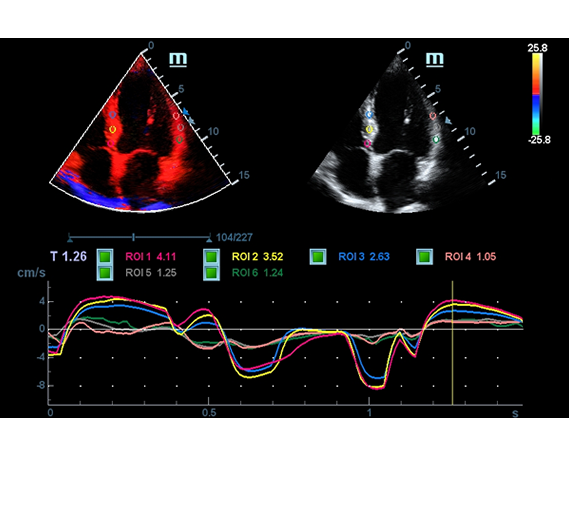

- TDI – Tissue Doppler Imaging

- TDI Quantification Analysis Software

- Tissue Tracking with Quantitative Analysis